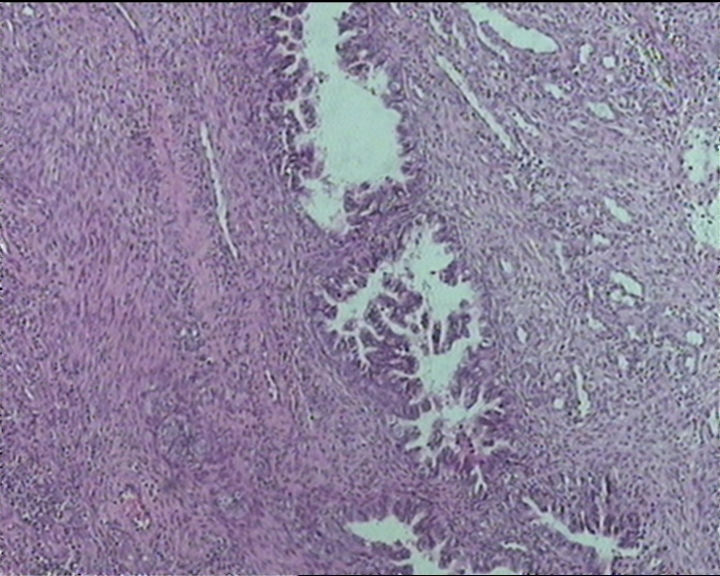

54岁女性,临床“宫颈息肉”送检;巨检:组织一块1。5*1CM,灰红。

输卵管粘膜化生

细胞及腺体均有异形,图6、11、16象有纤维间质反应,考虑高级别上皮内瘤变/原位癌,腺癌不能除外。

Sternberg病理学上诊断宫颈原位腺癌的标准是腺体的上皮去粘液分化,呈乳头状或筛网状增生,核分裂易见,这例显然达不到此标准。此例还是归入到腺上皮不典型增生为好。

It is benign. Benign endocervical polyp with tubal metaplasia.

杨老师说它是良性的,是个颈管内膜息肉伴输卵管上皮化生,良性